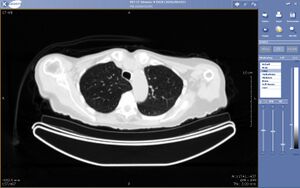

يمكن تعريف التطبيب عن بعد، أو الطب البعادي Telemedicine، على أنه نقل البيانات الطبية الإلكترونية (الصور، الأصوات، أفلام الفيديو، سجلات المرضى عالية الوضوح) من مكان إلى مكان آخر، من أجل صحة المريض وتعليمه أو مقدم الخدمة الصحية، وبغرض تحسين رعاية المرضى.

ويستخدم التطبيب عن بعد من قبل مقدمي الرعاية الصحية في عدد متزايد من التخصصات الطبية، بما فيها طب الجلد، وطب الأورام، والأشعة، والجراحة، وطب القلب، والطب النفسي، والرعاية الصحية المنزلية.